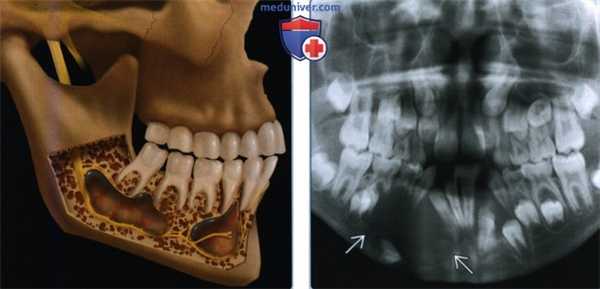

(Слева) На рисунке нижней челюсти (вид сбоку, кортикальный слой удален) показаны множественные кератокистозные одонтогенные опухоли, типичные для синдрома базальноклеточного невуса. Опухоли раздвигают корни зубов и смещают нервы.

(Справа) На ортопантограмме визуализируется крупное рентгенпрозрачное образование с экпансивным ростом в нижней челюсти слева, парамедианно, с выраженным смещением вовлеченных зубов.